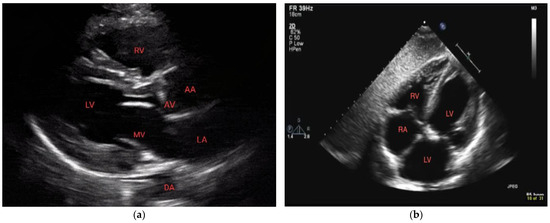

3.1. Technique